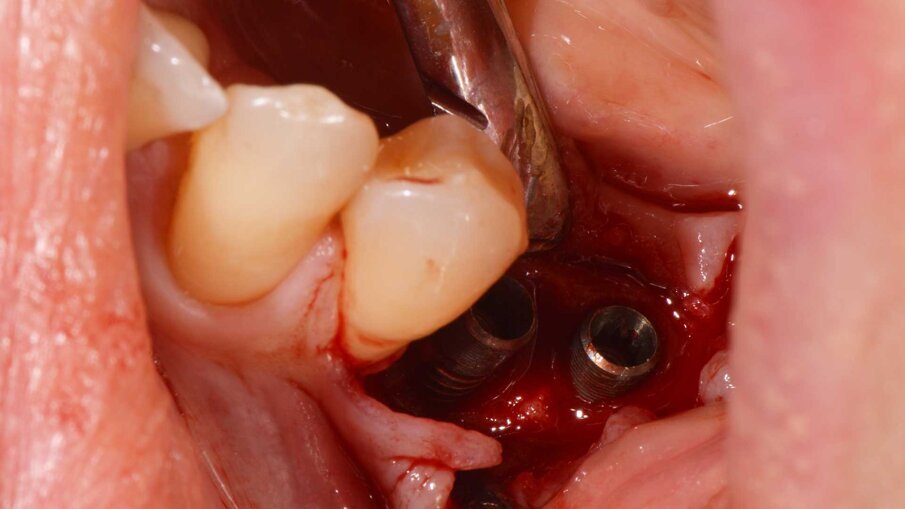

Un paziente di 47 anni, non fumatore e in buono stato di salute, all’esame clinico presenta una perimplantite diagnosticata dopo 7 anni di carico a livello degli impianti 3.5 e 3.6, con un sondaggio di 8 mm sull’aspetto mesiale dell’impianto 3.5 e di 4,5 mm sull’aspetto distale del 3.6. La radiografia conferma la perdita ossea attorno all’impianto distale e ancora più evidente a livello dell’impianto mesiale (Fig. 1). Si decide di trattare il caso chirurgicamente decontaminando la zona affetta, utilizzando il gel REGENFAST per potenziare il trofismo topico e inserendo la matrice Geistlich Fibro-Gide a sostegno dei tessuti molli coronali. Si procede con il trattamento chirurgico, esponendo il difetto per rimuovere il tessuto di granulazione (Fig. 2). La superficie implantare esposta è ulteriormente ripulita con ultrasuoni, spazzolino in titanio, passando all’interno delle spire e risciacquando con soluzione fisiologica e garze sterili (Fig. 3). Successivamente, il gel REGENFAST è dosato e posizionato direttamente all’interno del difetto perimplantare mediante spatolina o puntale (Fig. 4). La matrice Geistlich Fibro-Gide è ritagliata in modalità “Collagen-Ring” affinché possa essere posizionata attorno al collare implantare, sostenendo i tessuti molli che non collasseranno all’interno del difetto (Fig. 5). La matrice, grazie all’elevata porosità è completamente permeata di sangue permettendo la stabilizzazione del coagulo. La matrice viene ulteriormente imbevuta di gel REGENFAST così da potenziare i fisiologici processi rigenerativi (Fig. 6).

Fig. 2 - Esposizione del difetto e rimozione del tessuto di granulazione.